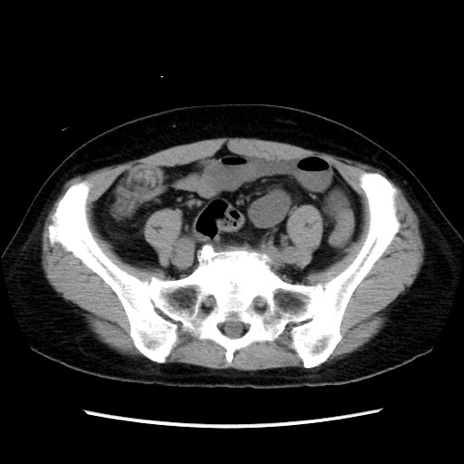

冠状断像

【症例】 50歳代女性

【主訴】 腹痛

【現病歴】前日生レバーを食べた。今朝に排便あり。 昼前に突然発症の腹痛を生じ、当院救急外来を受診した。

【既往歴】 子宮筋腫にてで子宮全摘後

【身体所見】 意識清明、腹部:平坦、軟、下腹部やや左を中心に圧痛・反跳痛あり、筋性防御あり

【データ】WBC 7800、CRP 0.07